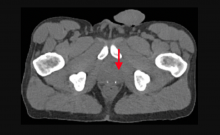

Yael Eshet, M.D., MSc, a diagnostic radiology specialist at Sheba Medical Center in Israel, was the lead author on a recent study that showed COVID-19 (SARS-CoV-2) vaccine adenopathy can persist more than 6 weeks. This swelling of lymph nodes is similar to what is seen cancer and infections and the new findings show it can last longer than 7-10 weeks. The current recommended time people should delay medical imaging is 6 weeks after receiving a COVID vaccine to avoid a misdiagnosis,[2] but this new study shows there is increased inflammation shown on PET-CT imaging for much longer.

These were the findings in the Radiology published study "Prevalence of Increased FDG PET/CT Axillary Lymph Node Uptake Beyond 6 Weeks after mRNA COVID-19 Vaccination."[1]

Researchers using fluorodeoxyglucose (FDG)-positron emission tomography (PET) have found increased FDG uptake in the lymph nodes of patients 7-10 weeks past their second mRNA-based Pfizer-BioNTech COVID-19 vaccination. This new information indicates a persistent immune response that could be mistaken on imaging exams for serious conditions like lymphoma over a much longer period of time.

Recent recommendations for post-vaccine lymphadenopathy advise scheduling routine imaging, such as screening mammography, before, or at least 6 weeks after, the final vaccination dose to eliminate false positive results. However, this new research showed that avid axillary lymph node uptake was present beyond 6 weeks after the second vaccination in more than 29% of the patients in the study cohort.

The authors stated “This study shows that avid axillary lymph node uptake on FDG PET/CT can be detected in more than a quarter of our patient population even beyond 6 weeks after the second dose of the mRNA-based COVID-19 vaccination. Compared to a previous study showing normalization of FDG uptake within 40 days of receiving an inactivated H1N1 influenza vaccine, we found uptake persistence even at 70 days. Physicians should be aware of this potential pitfall.”

Some images in this video are from another Radiology study, which showed PET tracer uptake at the COVID vaccine injection site and other examples of axillary adenopathy.[3]